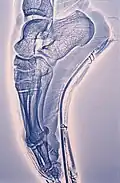

Xérographie du pied d'une danseuse dans son chausson faisant des pointes.

Les publications et conférences conjointes de Jean-Marie Galmiche et Paul Galmiche[3] ont vulgarisé les découvertes de l'Évolution en rendant au pied sa contribution fondamentale dans l'évolution du pré hominidé vers l'Homme[4],[5]. Cette évolution a commencé par la station debout[6] favorisant ainsi intelligence[7] et civilisation[8] et non l'inverse[9],[10].

Dons au musée international de la chaussure de Romans-sur-Isère[11] de moulages de pieds bandés dits pieds en lotus, de radiographies et chaussures chinoises du XIXe siècle.